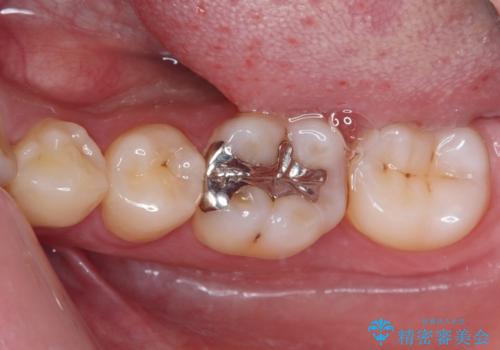

- 数年前他院にて治療した銀歯をやり替え希望の患者様です。

拡大鏡下で、銀歯、むし歯の除去を行い、セラミックインレーに適した形に整えました。